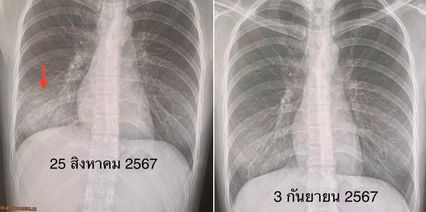

ผลตรวจร่างกาย มีไข้สูง 40.5 องศาเซลเซียส ระดับออกซิเจน 98 % ฟังปอดปกติ เอกซเรย์ปอดมีฝ้าขาวที่ปอดข้างขวาด้านล่าง  แยงจมูกส่งตรวจ PCR รหัสพันธุกรรม 22 สายพันธุ์ พบเชื้อแบคทีเรีย Mycoplasma pneumoniae เจาะเลือดตรวจพบว่า เม็ดเลือดขาวปกติ

แพทย์วินิจฉัยว่า ปอดอักเสบจากเชื้อแบคทีเรีย ไมโคพลาสมา Mycoplasma pneumonia ให้ยาปฏิชีวนะชนิดกิน  azithromycin และ moxifloxacin ผู้ป่วยดีขึ้นช้า ๆ ไข้ลอยอยู่ 5 วัน กว่าไข้จะลง ต้องให้น้ำเกลือ เพราะกินอาหารได้น้อยมาก ต่อมาอาการไอค่อย ๆ ลดลง ไม่เจ็บหน้าอก ไม่เหนื่อย แพทย์ติดตาม 9 วันต่อมา เอกซเรย์ปอดฝ้าขาวด้านล่างดีขึ้นมาก